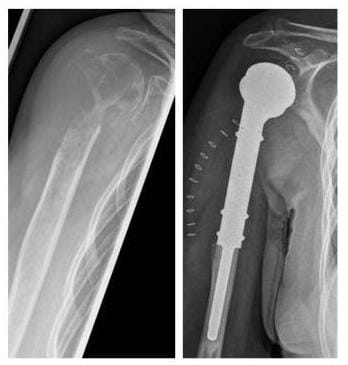

Wenn kein biologischer Ersatz möglich ist oder mit einem Kunstimplantat ein besseres Ergebnis zu erzielen ist, wird letzteres eingesetzt.

Röntgenbild der bösartige Tumor wurde entfernt und das betroffene Schultergelenk durch eine Tumorprothese ersetzt

Der bösartige Tumor wurde entfernt und das betroffene Schultergelenk durch eine Tumorprothese ersetzt. (Bilder: Orthopädie)